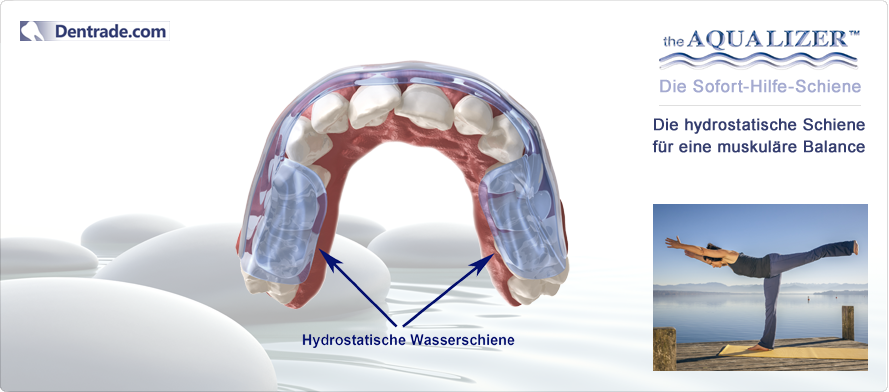

AQUALIZER™ - (аква+еквілібрація) - це наповнена водою накусочна шина, яка функціонує за гідростатичним принципом

Aqualizer™ - це єдина гідростатична накусочна шина, яка може бути застосована при лікуванні будь-якого пацієнта без попередньої підготовки та зуботехнічних робіт.

Завдяки водяному наповненню аквалайзер автоматично пристосовується до анатомічних особливостей пацієнта. Аквалайзер також добре зарекомендував себе при анамнезі та клінічній функціональній діагностиці як засіб діагностики та тимчасовий (лікувальний) засіб. Аквалайзер моментально компенсує неправильний прикус та встановлює збалансовану нервово-м`язову позицію нижньої щелепи. Позиція щелепи, при якій м`язи розслаблені, досягається за декілька хвилин. Для виготовлення нервово-м`язевого регістрату рекомендується тривалість носіння 1-2 тижні. За допомогою оклюзійних відбитків на пластмасовій поверхні аквалайзера візуалізується надмірний тиск при накусуванні чи скреготанні. Гідростатичний ефект також проявляється при застосуванні аквалайзера одночасно з іншою шиною.

Функціонування аквалайзера

Замкнена рідинна система аквалайзера діє динамічно та постійно, щоб збалансувати обидві сторони щелепи. Нижня щелепа завжди встановлюється в оптимальну позицію. Аквалайзер функціонує за гідростатичним принципом, який вперше було описано фізиком Паскалем. Згідно цього принципу, в замкненій рідинній системі тиск розподіляється рівномірно в усіх напрямках. Аквалайзер ідеально використовує цей принцип як саморегулююча шина. При цьому всі оклюзійні сили спрямовуються симетрично відносно осі, таким чином виникає стабільна оклюзія. Зуби просто можуть ковзати по гнучкій та гладкій поверхні прикусної подушечки аквалайзера. Гнучкі подушечки між обома оклюзійними поверхнями аквалайзера виключають усі контакти “зуб-до-зуба”. Функції пропріорецепторів зубів, м`язів та щелепних суглобів нейтралізуються. Звичайна, керована пропріорецепторами оклюзія усувається. Нижня щелепа, з допомогою розслаблених м`язів, може рухатися в комфортну позицію. Вже за декілька хвилин нова, розслаблена позиція усуває примусову болючу звичайну оклюзію пацієнта. В пацієнтів з хронічними болями цей процес триває трошки довше.